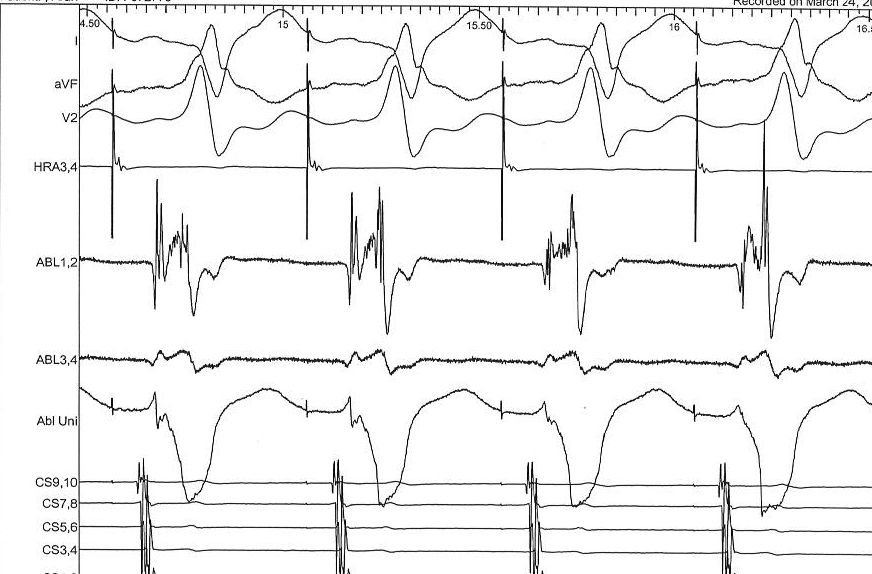

Ventricular tachycardia

Same concept

reset.jpg

Constant fusion

constant_fusion_a.png

Progressive fusion

constant_fusion_b.png

Example

entrainment_ecg.jpg

entrainment_egm.jpg